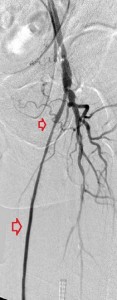

Key to images:

Top panel: Pre-intervention run-off angiogram of the left lower extremity showing, from left to right, irregular left common femoral artery (LCFA) arrowed on the 1st image, absent left superfical femoral artery (LSFA) or any bypass conduit on the 2nd image, sketchy descending collaterals from the left deep femoral (LDFA) that reconstitute a faint shadow of the left popliteal artery, arrowed on the 3rd image. The last 2 images faintly show three-vessel run-off below the left knee. The anterior tibial artery is most opacified, followed by the posterior tibial artery; the peroneal artery peeps through the upper edge of the last image. Note how weakly visible these vessels are due to the poor inflow from above.